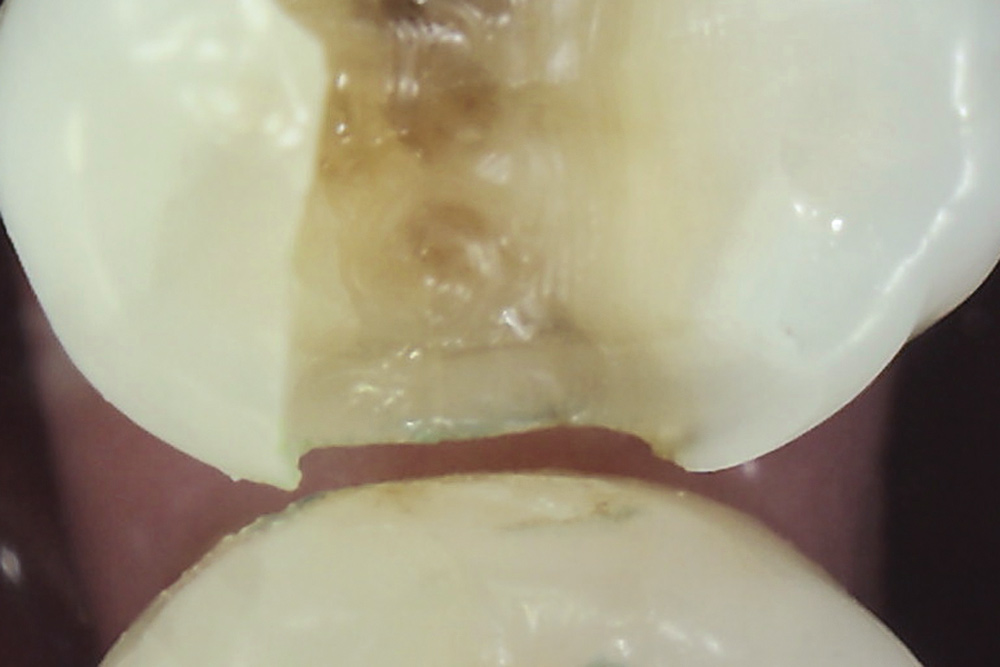

Once a significant asymptomatic enamel crack is diagnosed, to determine its extent the crack is exposed and traced using a minimally invasive exploratory fissurotomy as well as caries removal and/or existing restoration removal whenever indicated (Figure 6 and Figure 7).2,3,17 If the crack is limited to enamel and does not extend into dentin, it can be completely eliminated and treated similarly to caries whereby the condition of the remaining tooth structure dictates the type of the restoration placed and the materials used (Figure 8). For example, moderate-sized cavity preparations can support bonded direct intracoronal resin-based composite restorations (Figure 9).25 This is generally interpreted as cavity preparations in which the isthmus width is less than 50% of the intercuspal distance and the remaining enamel is sound and well supported by dentin. Occlusal adjustment, including removal of excursive interferences, might also be necessary to eliminate localized heavy occlusal forces that are predisposing the tooth to cracking.10,19,26 Occlusal guards also can be fabricated to protect teeth from the damage caused by ongoing bruxism.19

Fig 7. Existing restoration removal and crack fissurotomy revealing enamel crack (arrow) and caries in tooth shown in Fig 6.

Figure 7

Fig 8. Complete removal of caries and crack elimination by fissurotomy in tooth shown in Fig 7.

Figure 8